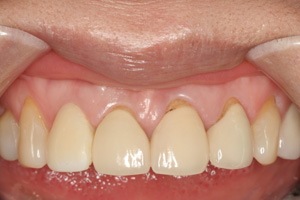

Clinical Cases